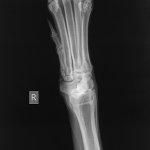

Here is his X-ray - they diagnosed minor inflammatory changes in his ‘wrist’, no bony changes on the long bones or shoulder, no bone fragments seen (they took 4 plates altogether).